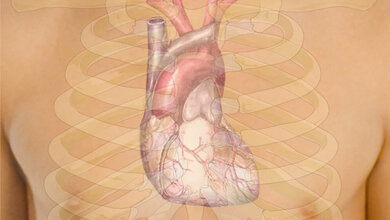

In einer neuen Studienarbeit haben Forscher/-innen der Universität Ulm und der Agaplesion Bethesda Klinik Ulm die Sterblichkeit von älteren Personen im Zusammenhang mit dem systolischen Blutdruck und dem Faktor „Gebrechlichkeit“ untersucht. Das Ergebnis: Das durch einen höheren systolischen Blutdruck bedingte Sterberisiko im Alter unterscheidet sich stark je nach der individuellen Fitness der Personen. Mit zunehmendem Lebensalter nimmt das Risiko für Bluthochdruck (Hypertonie) zu, da unter anderem die Gefäße an Elastizität verlieren. Mit dem Blutdruck steigt das Risiko für Herz-Kreislauf-Erkrankungen wie Schlaganfall oder Herzinfarkt. Deshalb zählt Hypertonie zu den großen vier Risikofaktoren.

Es gilt die Empfehlung, den systolischen Blutdruck meist medikamentös auf unter 140 mmHg zu senken. Jedoch kann eine starke Absenkung des Blutdrucks im Alter mit negativen Ereignissen wie Stürzen zusammenhängen. Dies sei auf die zunehmende autonome Dysregulation zurückzuführen. Das heißt, dass das körpereigene Kontrollsystem aus dem Gleichgewicht geraten ist. Dies kann im Zusammenspiel mit Störungen der venösen Durchblutung zu einem langanhaltenden Blutdruckabfall nach dem Aufstehen führen. Gleichzeitig gebe es Hinweise auf eine Verschlechterung der kognitiven Fähigkeiten, wenn der systolische Blutdruck bei Älteren deutlich unter 130 mmHg gesenkt werde, so die Uni Ulm. Auch andere Nebenwirkungen von blutdrucksenkenden Medikamenten wie Reizhusten, Allergien und Verdauungsprobleme seien bekannt.